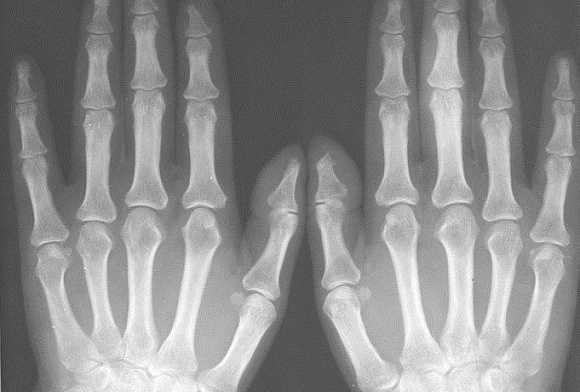

При болях, нарушении функции кисти или запястья только на одной руке для определения отклонений от нормы могут сделать рентген-фото лучезапястного сустава и кистей обеих рук.

Рентген кистей рук при ревматоидном артрите - важная диагностическая процедура, которая позволяет точно выявить стадию развития заболевания. Главными рентген-признаками данной патологии являются припухлости мягких тканей сустава. Также об артрите свидетельствует незначительное сужение межсуставной щели и визуализируемый остеопороз. На более поздних стадиях развития патологии будут видны эрозии костей, которые имеют вид некрупных краевых дефектов в суставных концах костей. В эпифизах костей фаланг пальцев могут виднеться округлые просветления.

При проведении рентгена кистей рук с функцией увеличения изображения можно выявить нарушение целостности замыкающих пластинок уже на первых стадиях развития ревматоидного артрита. По мере прогрессирования заболевания будет наблюдаться ухудшение картины - сустав будет становиться всё уже, появятся очаги эрозии, станет ярче выраженность остеопороза. В результате разрушения суставных концов кости могут появиться подвывихи.